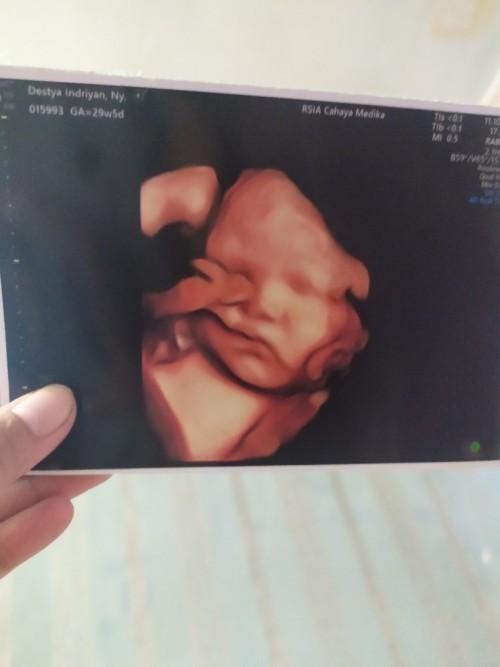

Baby girl kata dokter diintip waktu 26w skrg 29w